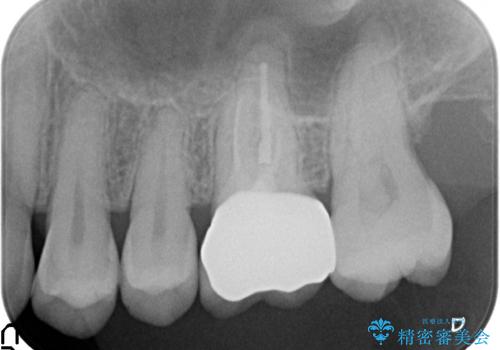

診査の結果、左上6が失活(歯の神経が死んでいる状態)しており根尖病変を認めたため、根管治療を行いました。

根尖病変の縮小及び症状の消失を確認後、オールセラミッククラウンによる補綴を行いました。

今回用いたオールセラミッククラウンはジルコニアフレームという白い素材の上にセラミックを盛っているため、審美性が非常に高いのが特徴です。

また、ジルコニアは人工ダイヤモンドの材料にも使われているほど高い強度を持っており、そのためオールセラミッククラウンは審美性だけでなく、奥歯やブリッジの補綴も可能とするクラウンです。